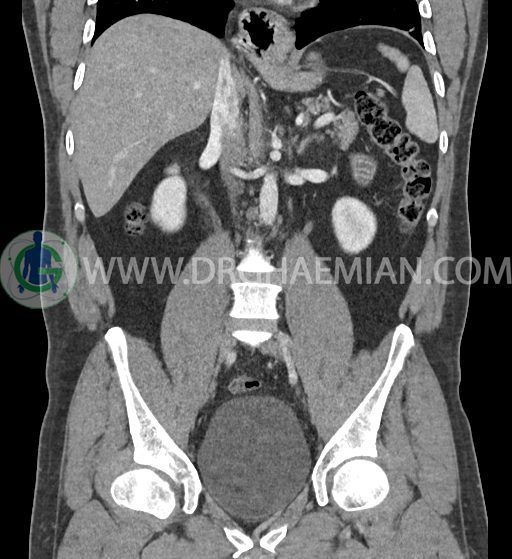

در سی تی اسکن اسپیرال شکم و لگن با کنتراست خوراکی و وریدی (مولتی دیدکتور 16 با مقاطع ظریف و بازسازی های ساژیتال و کرونال) :

-sliding hiatal hernia به ابعاد 60x44mm با جابجایی JE.junction و فوندوس معده به فضای مدیاستن خلفی دیده می شود.